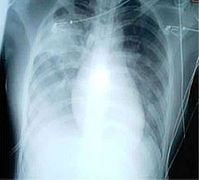

A chest radiograph showing bronchopulmonary dysplasia.